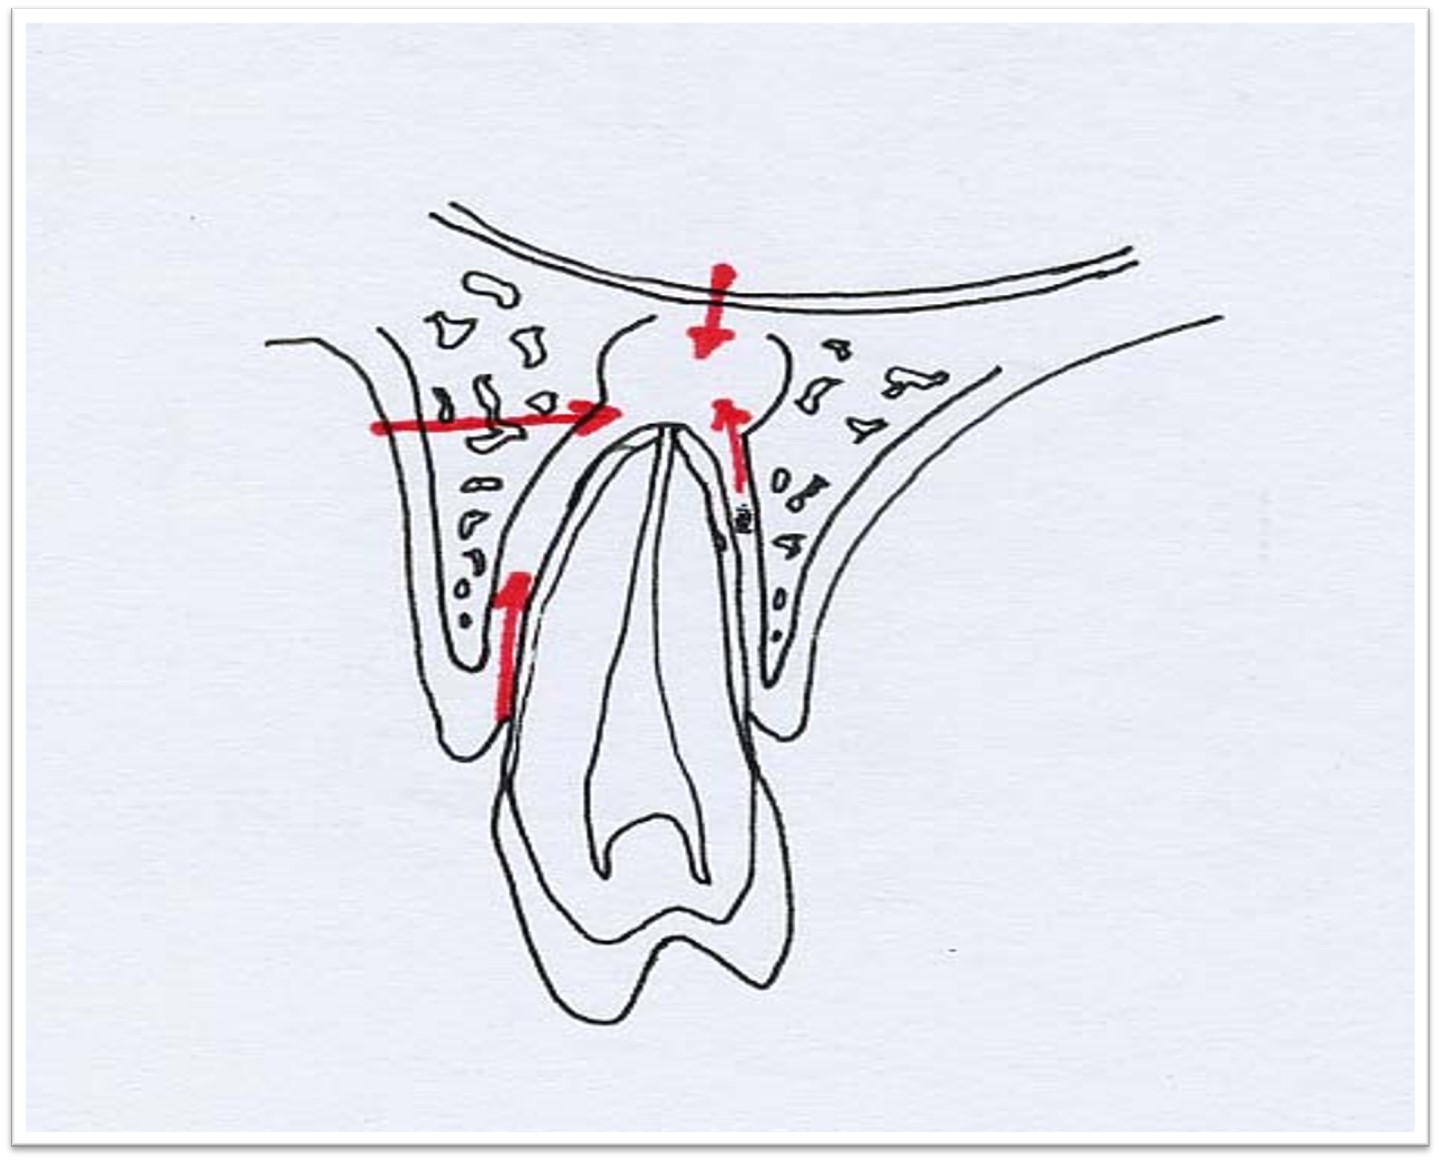

2. X线:根尖区牙周间隙增宽,或界限清楚的圆形透射影(图9.2-1)。

图9.2-1 根尖周肉芽肿X线

★根尖周肉芽肿的上皮来源(图9.2-4):Malassez上皮剩余;经窦道口长入的口腔黏膜上皮或皮肤;牙周袋上皮;呼吸道上皮。

图9.2-4 上皮性根尖周肉芽肿的上皮来源